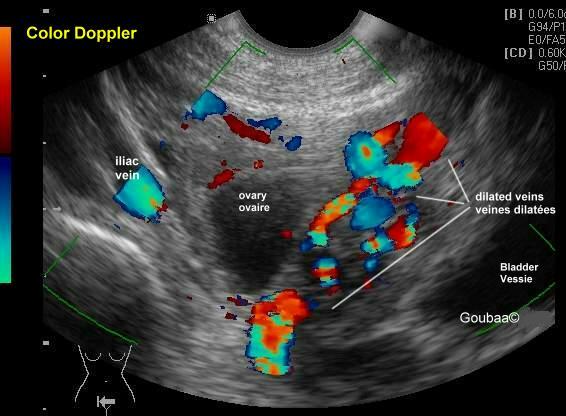

现在医学常用的手段有这么几种,超声,CT,核磁,静脉造影。

静脉造影虽然属于金标准,但是毕竟有创伤存在,不适合进行病人的筛查。而超声因为其无创性,是一个很有效的筛查手段,可以提供血管的动态指标,提示血管的直径和流速,但是对超声医生的要求比较高。CT和核磁检查呈现比较立体,更受青睐,需要体内注射一些对比剂。当然也有一些报道会采用腹腔镜探查的方式来判断,但是单纯因为可耐受的慢性腹痛去做这个手术,并不受待见。